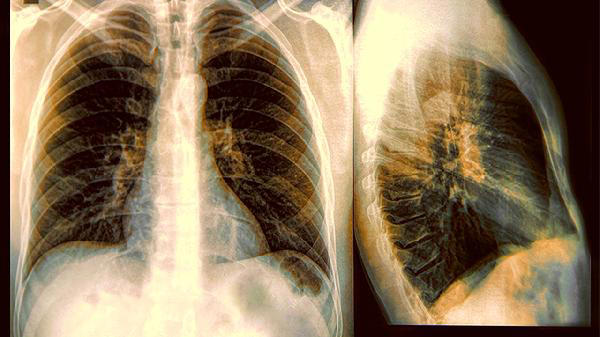

Theo Tổ chức Y tế Thế giới (WHO), khoảng 10 đến 20% bệnh nhân ung thư phổi trên thế giới là người không hút thuốc. Nguyên nhân có thể liên quan đến ô nhiễm không khí trong nhà, khí radon, khói bếp, yếu tố nghề nghiệp hoặc thói quen sinh hoạt kéo dài nhiều năm.